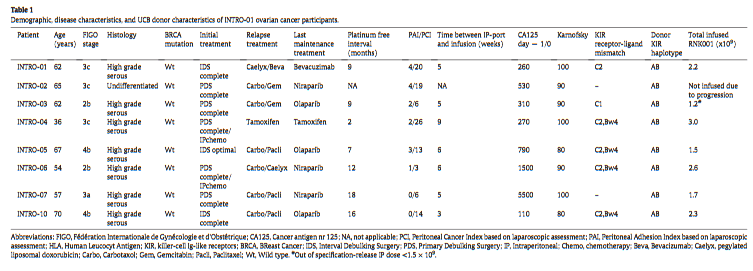

试验纳入12名在连续两个时间点通过血清CA125水平升高检测到二次复发EOC的患者,而无需因疾病进展而立即开始化疗。在RNK001输注之前,进行腹腔镜检查,放置Bard端口®进行IP输注,并评估液体是否能有效地分散到整个腹腔。第一组6名患者接受了RNK001的单次IP输注,没有接受非清髓性预处理化疗。第二组最终为6名预期患者中的1名,在−6至−3天接受环磷酰胺(Cy)900 mg/m2/天和氟达拉滨(Flu)30 mg/m2/天的预处理后,接受了RNK001治疗。两个队列都接受了相似剂量的RNK001产品(1.2-3.0×109个NK细胞)。

最终,7名患者接受了RNK001治疗:6名未接受Cy/Flu调理,1名接受Cy/Flue调理(图1B)。表1显示了RNK001制造的患者特征及其各自的UCB供体。尽管腹膜癌症指数(PCI)[28]最初并不被视为合格标准,但我们在治疗了第一组(INTRO-01、03和04)中的三名患者后修订了方案,并将36例患者中超过15例的PCI阈值作为排除标准。所有纳入患者的经皮冠状动脉介入治疗中位数为12.5(范围3-26;表1)。所有患者的Karnofsky评分均在80至100之间。在第二组中,一名患者在接受Cy/Flu化疗后接受了RNK001治疗,该患者耐受良好,没有严重毒性。